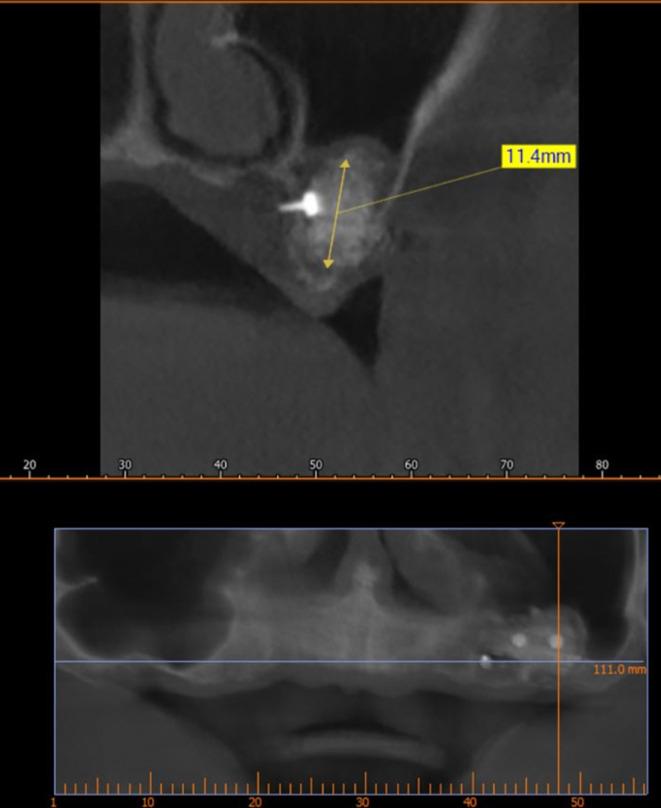

Dental implants provide a reliable treatment option for completely or partially edentulous patients. In case of a membrane perforation, the gap can be closed using a piece of resorbable collagen membrane or by suturing the Schneiderian membrane using a resorbable suture. The present study shows a new development in this technique, which involves modifying the design of the absorbable membrane and using pins to fix the membrane. This study concluded that the novel design of the collagen membrane and its fixation with the pins led to greater stability of the bone graft and led to subsequent bone gain that enables dental implantation. Still, this technique requires a histological study to determine the nature of the bone formed.

牙种植体为全口或部分无牙患者提供了一种可靠的治疗选择。如果发生膜穿孔,可以使用一片可吸收胶原膜或用可吸收缝线缝合施奈德膜来封闭间隙。本研究展示了该技术的一项新进展,即对可吸收膜的设计进行改进并使用销钉固定膜。该研究得出结论,胶原膜的新颖设计及其用销钉固定可使骨移植具有更高的稳定性,并导致随后的骨增量,从而能够进行牙种植。尽管如此,该技术仍需要进行组织学研究以确定所形成骨的性质。